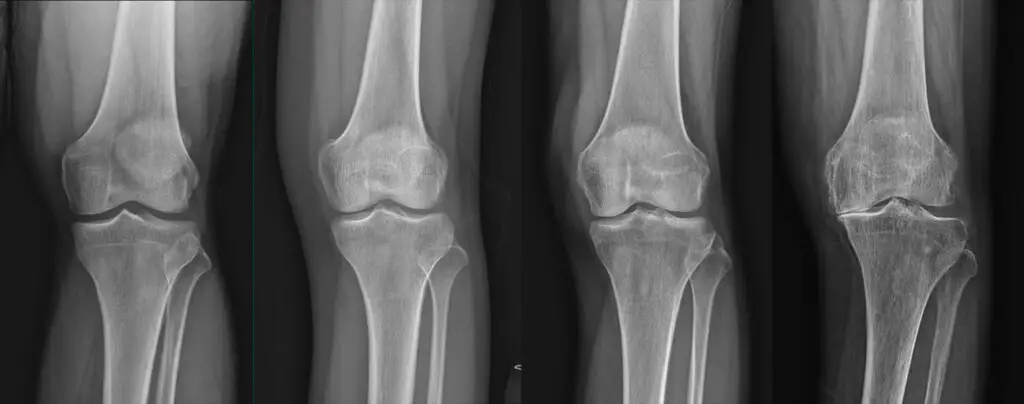

목디스크 원인

- 1. 자연적 노화

나이가 들면서 디스크의 탄력이 저하될 수 있습니다. 이는 자연스러운 노화 과정의 일부입니다.

이는 누구에게나 발생할 수 있는 일반적인 현상입니다.